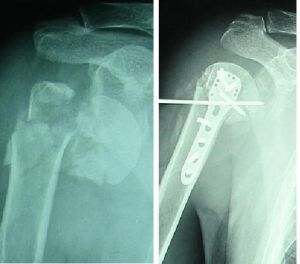

凡疑為骨折者應常規進行X線拍片檢查,可顯臨床上難以發現的不完全性骨折、深部的骨折、關節內骨折和小的撕脫性骨折等,即使臨床上已表現為明顯骨折者,X線拍片檢查也是必要的,可以幫助了解骨折的類型和具體情況,對治療具有指導意義。

骨折的X線檢查一般應拍攝包括鄰近一個關節在內的正、側位片,必要時須加攝斜位、切線位或健側相應部位的x光片。仔細閱讀x光片後應辨明以下幾點:

1、復位:是將骨折後發生移位的骨折斷端重新恢復正常或接近原有正常位置,以重新恢復骨骼的支架作用。復位的方法有閉合復位和手術復位、外固定架復位。

2、固定:骨折復位後,因為其不穩定,容易發生再移位,因此要採用不同的方法將其固定在滿意的位置上,使其逐漸癒合。常用的固定方法有:小夾板、石膏繃帶、外固定支架、牽引制動固定等,這些叫外固定。如果通過手術切開上鋼板、鋼針、髓內針、螺絲釘等,就叫內固定。